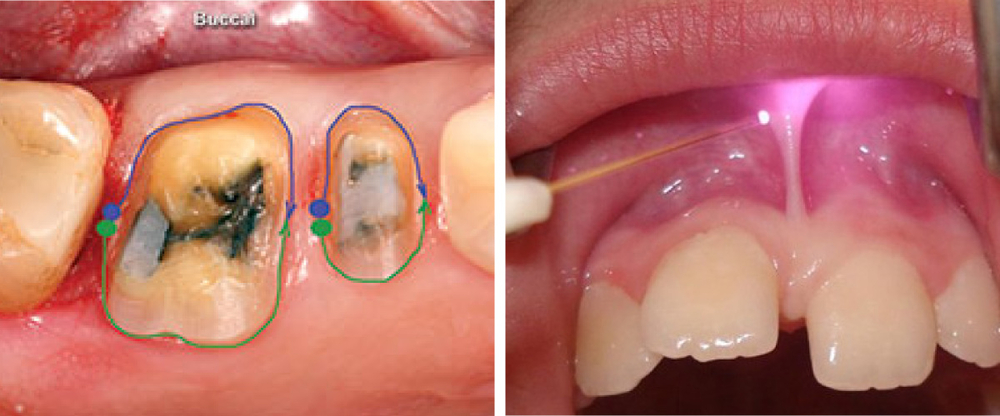

Diode lasers are utilized across a wide range of dental procedures, offering precise soft tissue sculpting. Laser treatment reduces discomfort, speeds up healing times, and improves treatment outcomes.